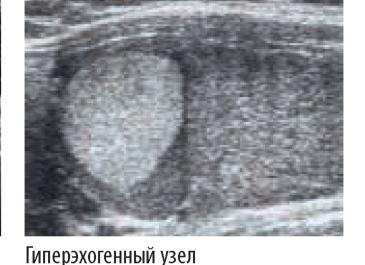

3. Гиперэхогенность: указывает на разрастание тканей либо отложение кальциевых солей. При этом участки отображаются светлыми оттенками.

Гиперэхогенность – имеет неоднородную структуру. Ткань в этом случае имеет повышенную акустическую плотность и говорит об увеличении объема соединительных тканей или об отложении кальцинатов.

5. Аденома – гиперэхогенный узел светлого цвета. Вокруг него имеется гипоэхогенный темный толстый ободок. Это участок отека и сосуды внутри узла.